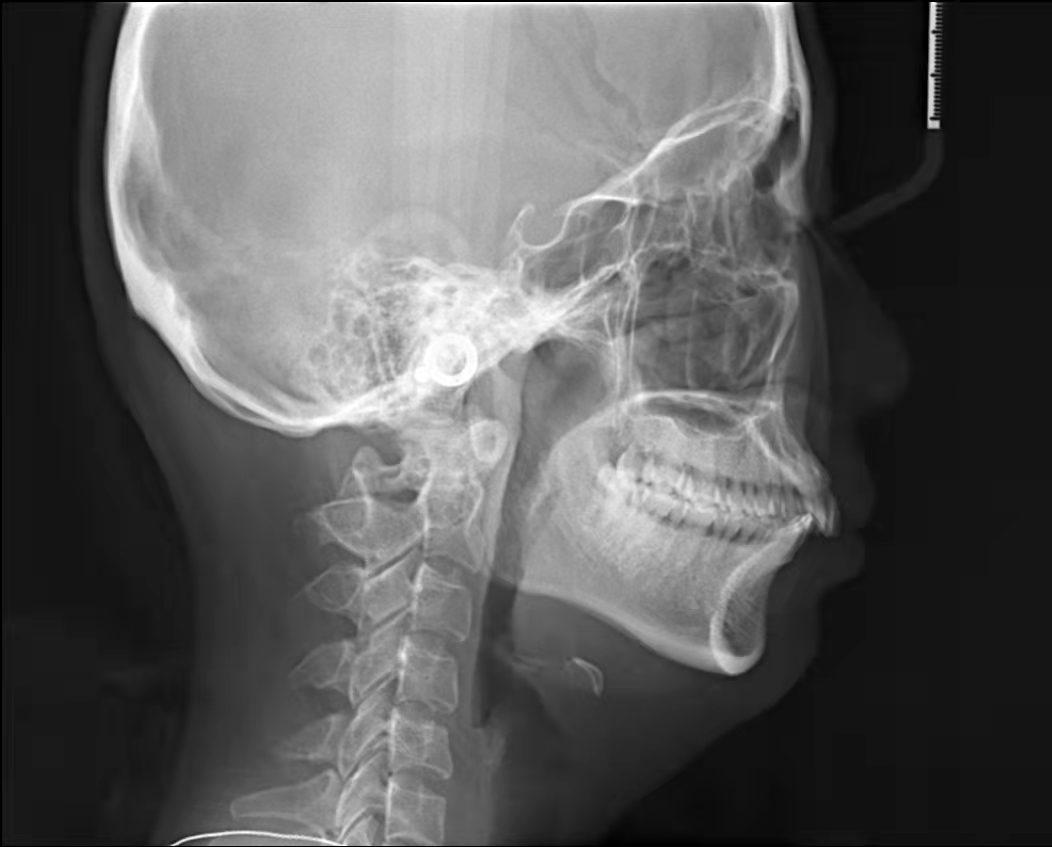

嘴凸不說下巴還后縮

沒有美美的側(cè)顏殺怎么拿下心動男孩呢!!

咱不提倡整容!但咱天生的下巴要給他使喚出來吧!所以很多妹紙沒有下巴有可能不是天生的呢!

4、齙牙造成面部變形。臉型在人體美中占有重要的位置,臉型的美麗與諧調(diào),是由的牙列來維持的。齙牙咬合受影響,導(dǎo)致面部不協(xié)調(diào),從而加速面部衰竭,由于臉部的骨骼結(jié)構(gòu)也會影響皺紋形成,齙牙嘴型往前凸,恰好在法令紋位置形成凹陷,法令紋自然會加深。而且牙槽骨或整個頜骨因缺乏正常咀嚼氣力的刺激,將會逐漸蛻變、萎縮,造成下巴的長度變短,面頰部和四面肌肉松弛,甚至?xí)斐擅娌孔冃巍?/span>